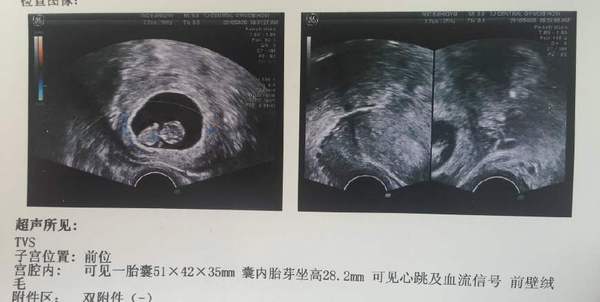

39天的时候做的B超,有过来人告诉我:“男娃的孕囊是椭圆的,女娃的孕囊则接近正圆。”我家娃的孕囊圆的快接近用圆规画出来的一样。